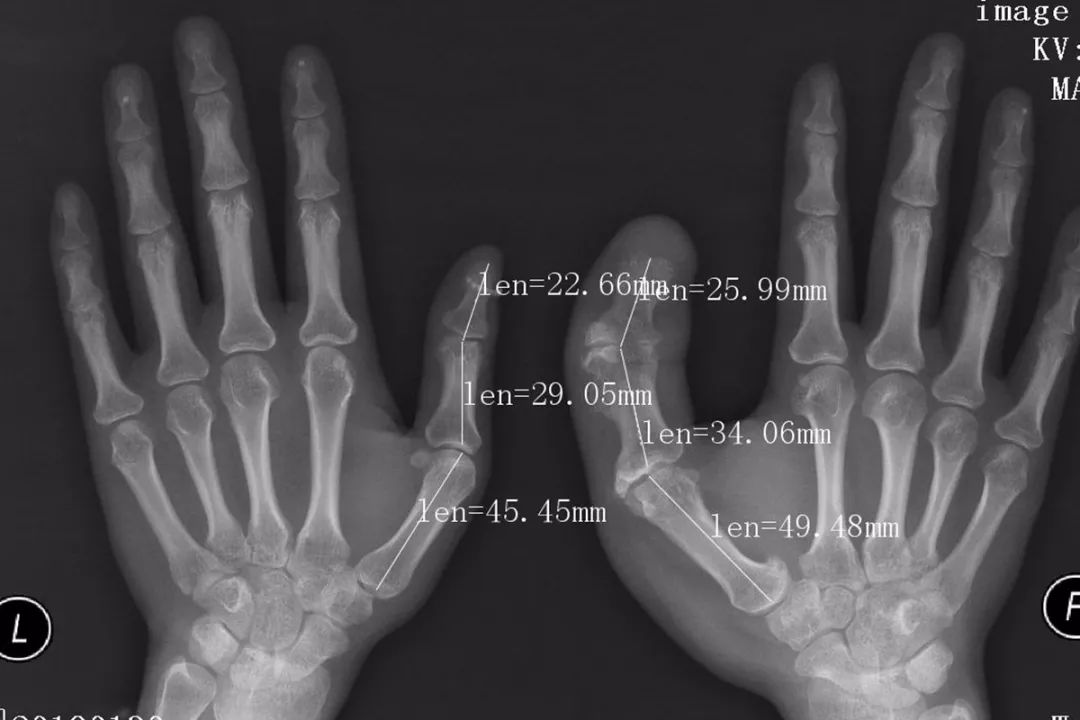

(术前通过X线片测量并设计截骨方案)

一期手术前,医生通过X线片测量手术切口并设计截骨方案,截骨后,拇指指骨已经接近正常大小。术后病理证实,何女士的巨指症属于典型的神经脂肪瘤病。通过制定个性化手术方案期并进行分期的手指外形的修复,目前巨大的手指外观得到了很好的改善。